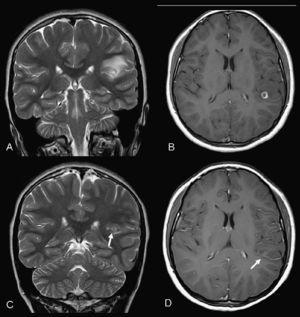

Caso clínicoMujer de 12 años de origen boliviano (residente desde hace 15 meses en España), que ingresa por episodio de desconexión del medio, sialorrea y disartria de 20 min de duración, seguidas de estupor e hipotonía de 15 min de duración. Recuperación completa. No refiere antecedentes de interés. La RM cerebral (fig. 1) muestra una lesión esferoidea temporoparietal izquierda de 9 mm rodeada de edema con realce periférico tras la administración de gadolinio, lo que plantea el diagnóstico diferencial entre quiste cisticercoide y astrocitoma. Las serologías para cisticerco en sangre y líquido cefalorraquídeo son negativas y la valoración oftalmológica no muestra quistes. Tras tratamiento con mebendazol (21 días) y prednisona (1 mg/kg) la paciente está asintomática desde el punto de vista neurológico. La RM de control (6 meses después de la crisis) evidencia una disminución del diámetro lesional y la desaparición del edema vasogénico.

Figura 1. A) Resonancia magnética (RM) al diagnóstico turbo spin echo (TSE) T2 coronal. B) RM al diagnóstico spin echo (SE) T1 poscontraste axial. C) RM postratamiento TSE T2 coronal. D) RM postratamiento SE T1 poscontraste axial. Lesión quística con un pequeño nódulo mural, subcortical temporoparietal izquierda de 9 mm de tamaño, con importante edema vasogénico y realce anular compatible con un estadio vesiculocoloidal. En el control postratamiento (flechas) ha disminuido de tamaño, con desaparición del edema y un fino realce periférico residual (estadio nodulogranular).